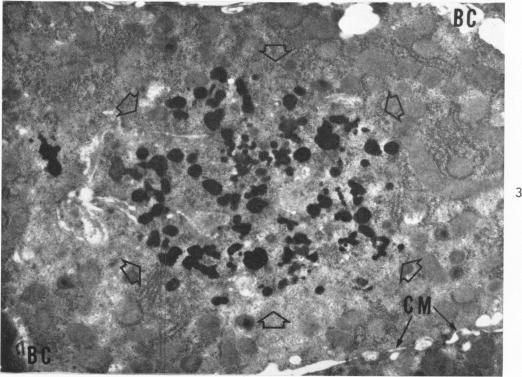

The Movement of Iron-Laden Lysosomes in Rat Liver Cells During Mitosis.

Am J Pathol. 1965 May;46(5):803-27.